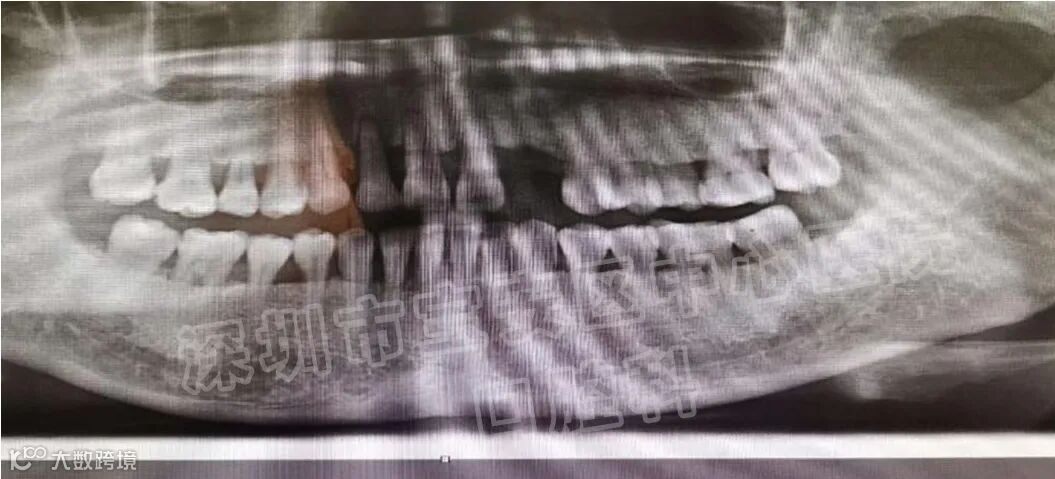

牙周病 是牙齿支持组织,包括牙龈、牙骨质、牙周韧带和牙槽骨因炎症所致的一种疾病,是最常见的口腔疾病之一,也是导致牙齿丧失的一个主要原因。但患者并非所有这些组织都同时患病,视局部炎症的轻重及范围,牙周病可分为龈炎和牙周炎二大类。

经过上述治疗之后,大多数患者的牙周炎症可以得到消除,松动的牙齿慢慢稳固,患者的咀嚼功能明显提高。但是,经过牙周基础治疗之后,部分患者仍然会有个别牙齿,甚至多颗乃至整个牙弓中的余留牙齿松动,难以行使正常的咀嚼功能,一旦出现上述问题,则需要采用牙周炎手术治疗。牙周翻瓣,牙周再生,骨再生等手术去恢复牙龈炎症,牙槽骨吸收等问题

修复治疗成为牙周炎综合治疗的重要组成部分,牙周炎的修复治疗是在牙周基础治疗的基础上,通过修复学的方法来改善患牙的松动、移位及咀嚼无力等症状。牙周炎的修复治疗主要包括调牙合、正畸疗法和牙周夹板固定等。